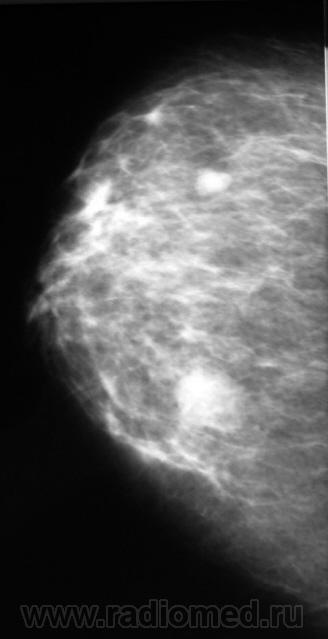

Ещё одна интересная маммография

Жалоб пациентка не предъявляет, просто иногда ощущает дискомфорт в мол.железах.

Кистозный ФАМ с одной стороны просто ФАМ с другой (где право-лево не указано на снимках)

Где прямые, где косые? Вероятно кисты, но могут быть и фиброаденомы, надо УЗИ и при кистах - пункционное удаление содержимого, при фиброаденомах - секторальная резекция.

А, мне, что-то больше симпатично, как "фиброаденомы".

Гадать кисты это или фиброаденомы без УЗИ - дело не благодарное, почему кисты ставлю на первое место потому, что чаще кисты бывают множественными.